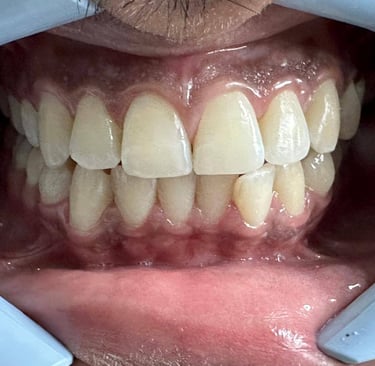

Aparelhos ortodônticos

Os aparelhos ortodônticos corrigem e

alinham os dentes. Além dos métodos

metálicos tradicionais, os aparelhos invisíveis

(como o Invisalign ) são discretos e práticos,

proporcionando um sorriso alinhado de forma

confortável e estética.